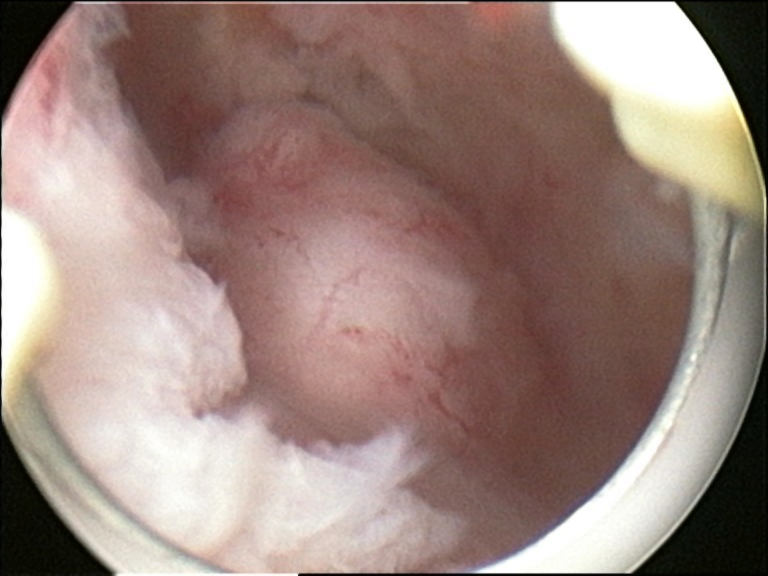

4. 4. 자궁경 검사

자궁경 검사도 자궁근종 진단에 사용될 수 있다. MRI는 T1WI에서 저~등 신호, T2WI에서 저 신호를 나타내는 자궁근종의 특징적인 소견을 보여주며, 혈행 장애로 인한 다양한 이차성 변화(유리화, 낭포화, 석회화, 지방 변성, 괴사 등)를 관찰할 수 있다. 종양 직경이 8cm를 초과하면 악성 가능성을 고려해야 한다.

5. 1. 점막하 근종 (Submucosal myoma)

점막하 근종은 자궁 내막 아래의 근육에 위치하며 자궁강을 변형시킨다. 이 위치에 있는 작은 병변조차도 출혈 및 불임을 유발할 수 있다.[6] 강 내에 유경 병변은 자궁강내 근종이라고 하며 자궁 경부를 통과할 수 있다.2011년 이후 FIGO는 근종 분류에 대한 합의 논문을 발표했는데, 0부터 8까지 분류한다. 이는 PALM COEIN 분류의 일부이며 임상 실습 및 연구에서 가장 자주 사용된다.[19]